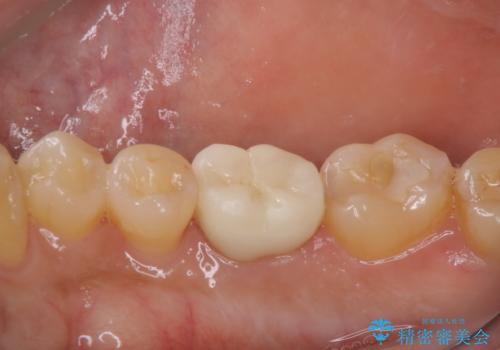

精密根管治療とオールセラミックで補綴治療を行いました

精密根管治療で痛みはすぐに消退しました。

数ヶ月後には根分岐部の病変もなくなっていました。